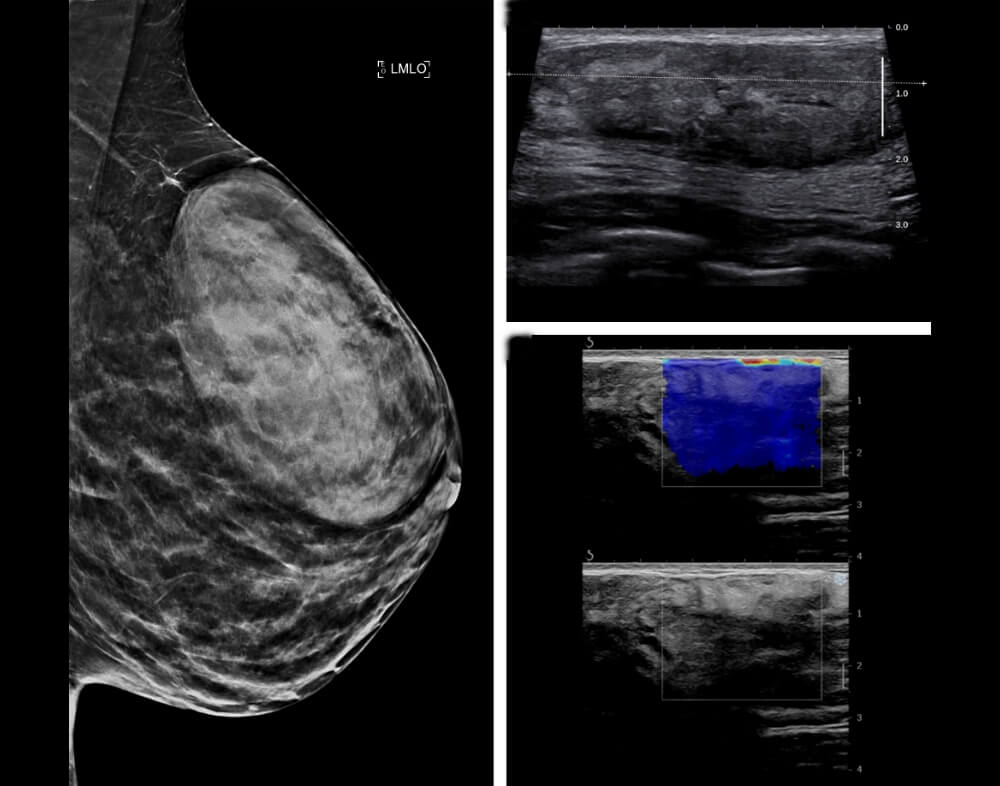

Στην μαστογραφία συνήθως εμφανίζεται σαν μια καλά περιεγραμμένη μάζα με άλλοτε άλλη πυκνότητα.

Στο υπερηχογράφημα ο εξεταστής μπορεί να μην αντιληφθεί την ύπαρξή του αν δεν αναφερθεί ψηλαφητό εύρημα ή αν δεν υπάρχει εύρημα στη μαστογραφία που να κατευθύνει την προσοχή του κατά την εξέταση.